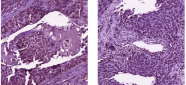

| Large clusters of tumor (40) | Tumor with infiltration (48) | Ring structured tumor (43) |

To interpret the histopathological features indicating a high risk of recurrence, we evaluate the association between each tile cluster and recurrence based on our survival model. As the hazard proportion are computed by , we apply an exponential function to the Cox regression coefficients corresponding to the cluster features in order to obtain a measure of feature importance, reported in Appendix C. If the result is greater than one, then the corresponding cluster is positively associated with recurrence.

Figure 3 shows the description on the dominant morphological pattern visible in the top clusters associated with high risk of recurrence in the Cox regression. We select tiles with highest probability belonging to each cluster. The selected clusters and tiles were reviewed by a pathologist who summarized the dominant pathological features in the cluster. High risk histopathological features include large tumor clusters, tumors with infiltration, and ring structure of tumor cells. This may yield novel hypothesis to explore the causes of LSCC recurrence. A number of small outlier clusters also occur in our analysis, like cluster 49, that indicate frozen or slicing artifacts occasionally occuring in different parts of WSIs. Future studies can potentially exclude these tiles, as they are irrelevant to biological features.